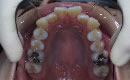

アゴが小さいために、歯の生える場所が足りず、でこぼこだったり、重なり合って歯が生えている状態。歯ブラシがゆき届かず虫歯や歯周病に注意が必要です。

原因アゴが小さい 歯が大きい 乳歯の虫歯や奥歯の欠損(早期欠損)